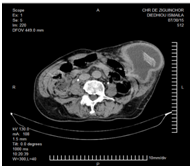

We report the case of a 75-year-old man, who was received in consultation for an abdominal painless mass of the left flank, gradually increasing in volume. His medical history related a midline xypho-pubic laparotomy in 1970 for an unspecified cause of peritonitis. The physical examination indicated a good general condition, colored mucous membranes, and a painless and irreducible mass of soft consistency measuring 15x13 cm in the left flank, Figure 1. We noted a midline xypho-pubic laparotomy scar. The rest of the physical examination showed no specificities. The blood count Biology showed a 5000/mmᵌ white blood cell count, a 11.9g/dl hemoglobin level and a 327000/mmᵌ platelet count. The creatinine serum was 10mg/l and the urea 0.20 g/l. The computed tomography (CT) showed a parietal liquid collection of the left flank measuring 15x13 cm with a thickened and regular wall containing a dense formation of lamellar appearance foretelling of a foreign body herniated to the lateral wall Figure 2. A general anesthesia was performed on the patient for the surgical exploration. The surgical exploration by incision at the level of the mass revealed a seroma shell containing 21 of shady liquid and a Delbet blade measuring 20 cm long in an extra-peritoneal position Figure 3. We carried out a complete excision of the hull taking out the Delbet blade without any peritoneal/bloodshed, and a myorraphy. The postoperative management was simple. The patient was allowed to resume home four days after surgery (Figure 1–4).

Figure 2 Parietal liquid collection with a lamellar formation foretelling a foreign body